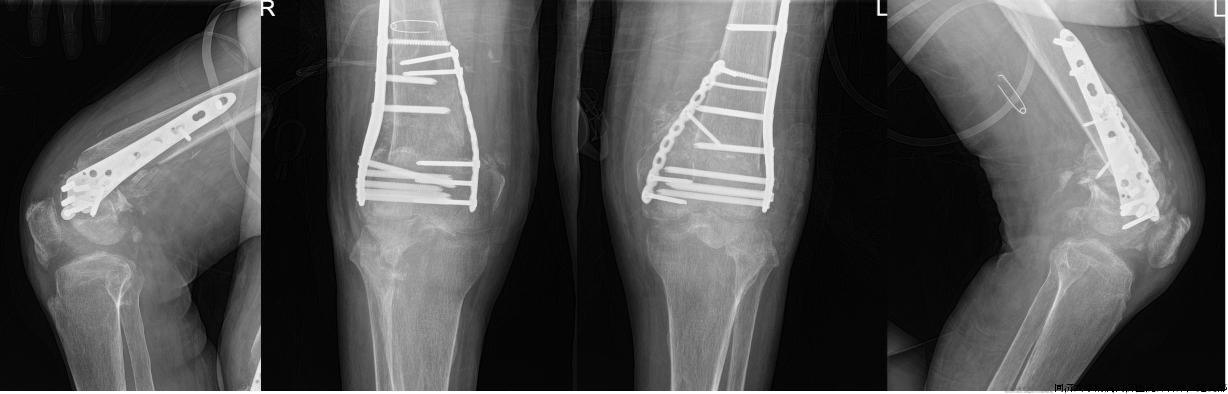

5月22日,辜老师住进了同济医院骨科创伤病区,樊健主任组织了科内讨论,对手术入路、固定方式、可能出现的并发症、应急方案及预期效果都进行了明确,家属也给予了充分的理解及支持。5月27日,经过充分的术前准备,在麻醉科杨君君医生、刘健慧主任及手术室姚英护士长等人的通力配合,并采取有效措施拮抗呼衰等高风险情况下,樊健主任和姜超主治医师基于前期充分准备,使用手术导板等辅助工具,以最快速度、最小损伤完成截骨、对线、有效内固定等手术操作,重新恢复双侧患膝关节解剖(图2)。术后经过重症医学科张磊主任等监护治疗后,辜老师不久即回到了骨科普通病房,床位医生姜超博士及骨科康复高翔医生等随即来到床边进行康复指导。当看到自己双侧膝关节恢复到正常位、日后又能站立时,辜老师及家属激动万分。

图2.术后X线:双侧膝关节结构恢复